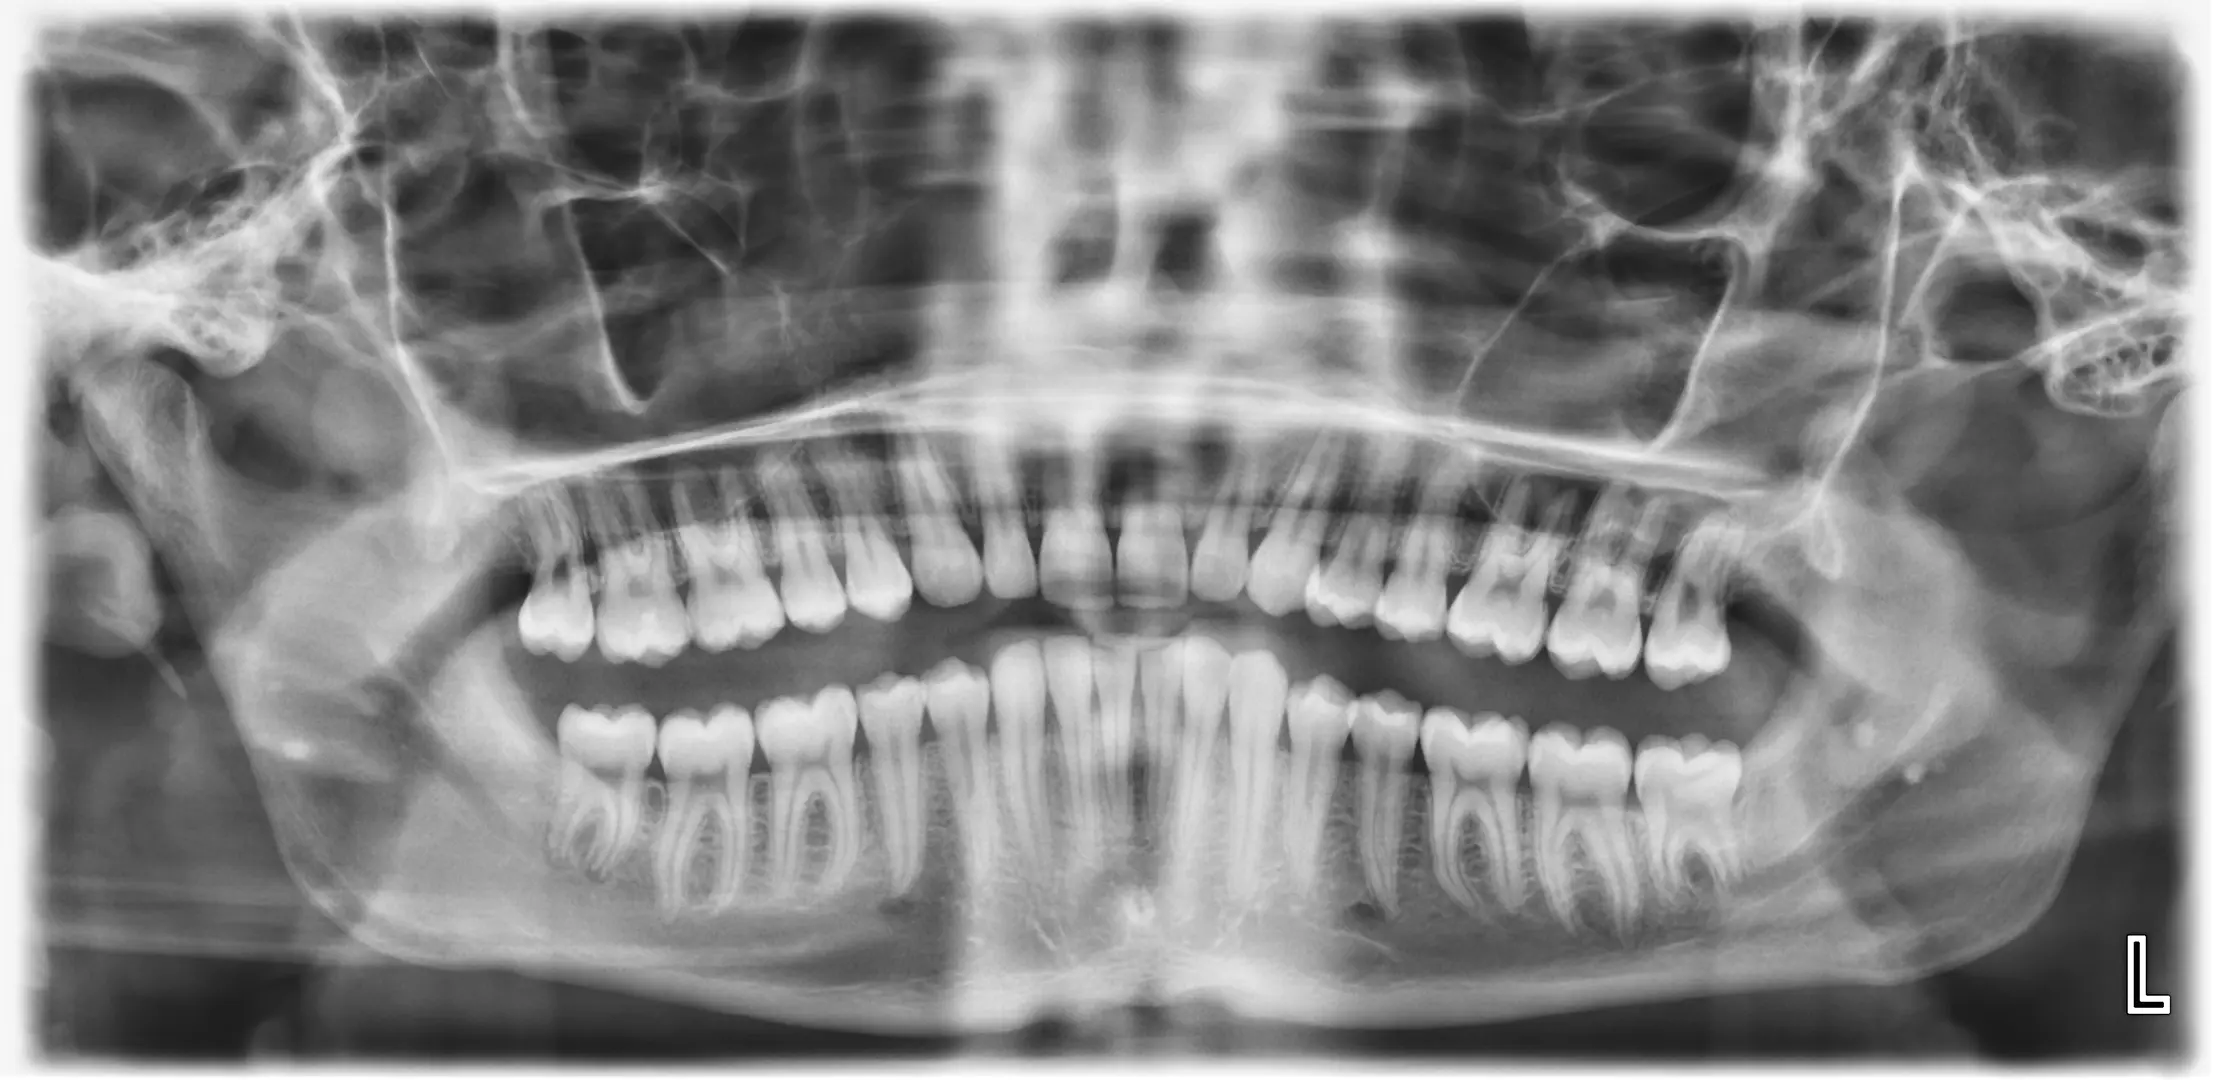

Představujeme vám naši stomatologickou ordinaci nacházející se nedaleko centra města Uherské Hradiště. Kromě OPG a intraorálního rentgenu vás u nás čeká usměvavý personál, který se postará nejen o prevenci, ale i návrat vašeho úsměvu.